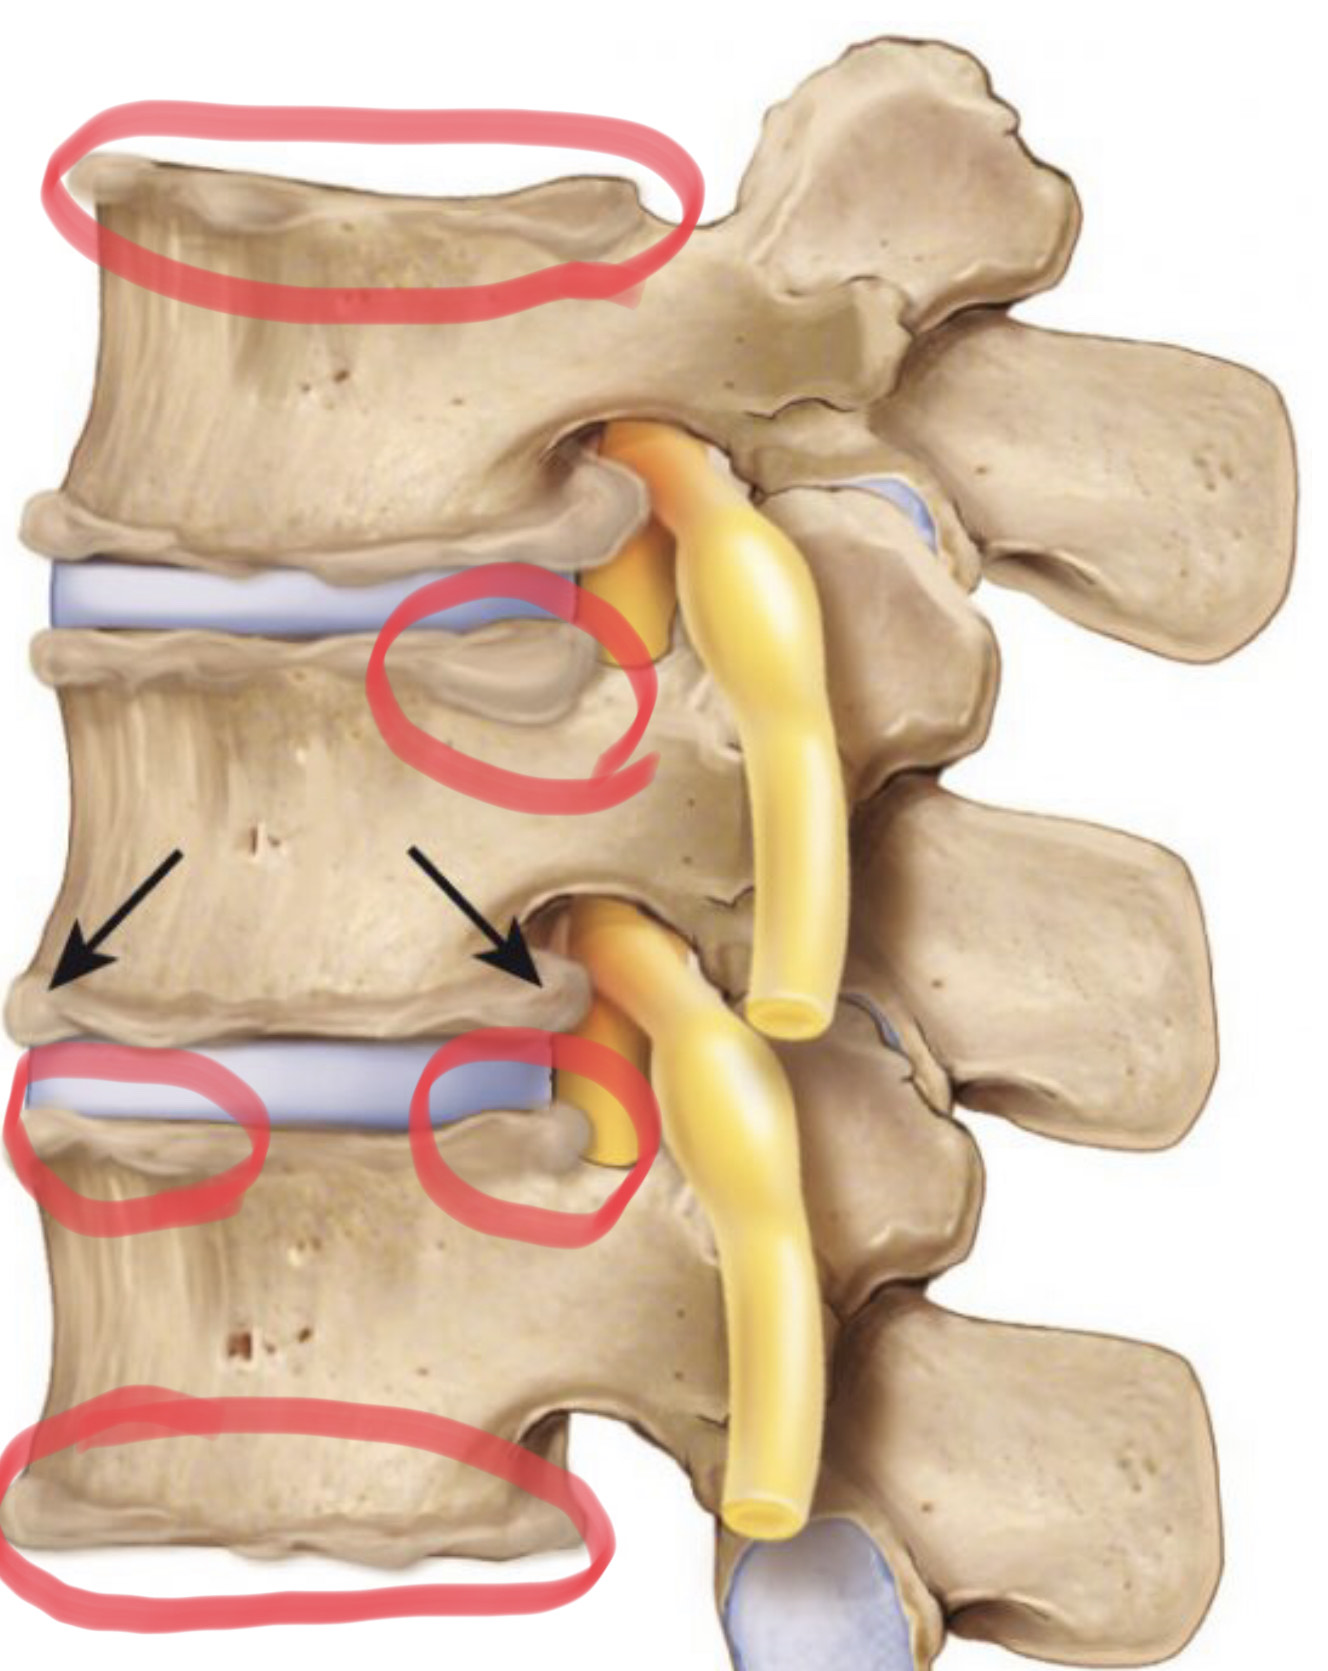

Če se le ti znižajo, vplivajo posledično na obliko in sestavo vretenc, saj se prostor med njimi zmanjša in vretenca drgnejo in pritiskajo druga na drugo. Zato degenerativno stanje medvretenčnih ploščic, sklepov in ligamentov posledično lahko povzroča spondilozo.

Pojavi se s staranjem, preobremenitvami, z vnetji ali po poškodbah (prekomerna telesna teža, kajenje in genetika tudi spadajo med dejavnike tveganja) zaradi slabe presnove oz. dehidracije medvretenčnih ploščic. Poleg dehidracije opazimo še izbočene ali znižane ploščice, zadebeljene ali oslabljene ligamente in izrastke na vretencih. Ti izrastki na vretencih se imenujejo osteofiti.

Spondiloza ima štiri pogoste spremljevalce: Degeneracija diskov, osteofiti, osteohondroza in stenoza. Vsa stanja in izrazi se povezujejo. Degeneracija diskov povzroča ožanje ali stenozo. Stenoza kot vemo iz mojih prejšnjih člankov v grščini pomeni- OŽITEV. Ožitev pa povzroča spondilitične izrastke kot so osteofiti. Osteohondroza pa pomeni nič drugega kot odmiranje kosti. Brez skrbi, gre zopet za stanje, ki zveni huje kot je v resnici. Osteohondroza se pogosto pojavi namreč tudi pri mladih in športno aktivnih, rastoči populaciji. Zaradi hitrega prirastka ali pa pritiska na vretenca lahko določen del le tega ostane slabo prekrvavljen, in ta del kosti postaja šibek in porozen. Temu procesu nekroze, odmiranja, nato sledi faza rasti, ki pa je veliko bolj čvrsta in agresivna. Takšna kost se lahko hipertrofično zaraste in poveča. To pa izzove bolečine v kolikor ti izrastki kosti pritiskajo na živčne korenine. V kolikor ne pritiskajo, ni nobenih težav, kljub temu, da lahko MRI kaže veliko izrastkov.

Vse te diagnoze lahko prizadenejo katerikoli del hrbtenice, najpogosteje vratni in ledveni del. Na začetku bolečina ni pogosto prisotna, razen občasnih neprijetnih občutkov. So pa opazne manjše spremembe ploščice, ki lahko privedejo do sprememb v hrbteničnih krivinah zaradi česar je možna tudi kompresija korenin živcev. Poleg naštetega nekateri opažajo pomanjkanje energije tekom dneva in nižanje telesne višine.

V nadaljevanju se degenerativne spremembe stopnjujejo, posamezniki še vedno lahko opažajo nižanje telesne višine, pojavijo se kostni izrastki na telesu vretenca (osteofiti), spremembe v drži so bolj izrazite, pojavi se lahko tudi spinalna stenoza. Pri huje napredovani obliki pride do izgube sklepnega prostora, vretenca drgnejo eno ob drugo, se pri nekaterih celo združijo, prisotne so močne bolečine, ki lahko vodijo v psihološke motnje.